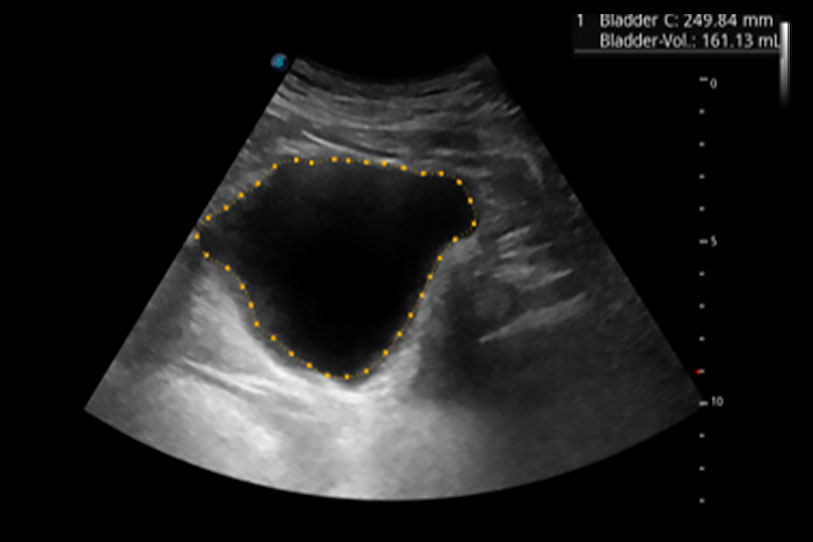

一鍵自動(dòng)識別膀胱壁及自動(dòng)測量膀胱容積,不受膀胱形狀和大小的限制,幫助醫(yī)生快速精準(zhǔn)獲得測量的數(shù)據(jù)。